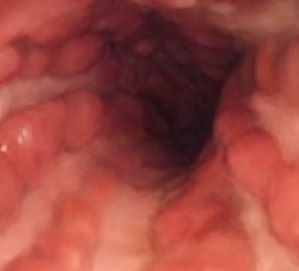

크론병의 증상은 경증부터 중증까지 다양하며 점진적으로 나타나거나 갑자기 나타날 수 있습니다. 일반적인 증상으로는 지속적인 설사, 복통 및 경련, 혈변, 궤양, 식욕 감소, 체중 감소 등이 있습니다. 심한 경우에는 발열, 피로, 관절염, 눈 염증, 피부 질환, 어린이의 성장 지연 등을 경험할 수 있습니다. 또한 증상 기와 무증상기(특별한 처치 없이 증상이 회복되어 아무런 증상도 나타나지 않는 시기)가 반복됩니다. 이외에도 장의 기능 이상과 관련 없이 관절통, 관절염이 나타나기도 합니다. 피부, 눈, 간, 신장에 이상이 생기기도 합니다. 골밀도가 감소하여 골다공증이 생기는 경우도 있습니다. 진단에는 환자 병력, 신체검사 및 다양한 검사가 조합되어 이루어집니다. 이러한 검사에는 혈액 검사, 대변 검사, 대장 내시경 검사, 내시경 검사, CT 스캔이나 MRI와 같은 영상 검사가 포함될 수 있습니다. 특히 내시경 검사에서 종주형 궤양과 자갈밭처럼 보이는 조약돌 점막 형태를 관찰할 수 있습니다. 크론병의 증상은 과민성 대장 증후군(IBS) 및 체강 질병과 같은 다른 질환과 유사할 수 있으므로 정확한 진단이 중요합니다.